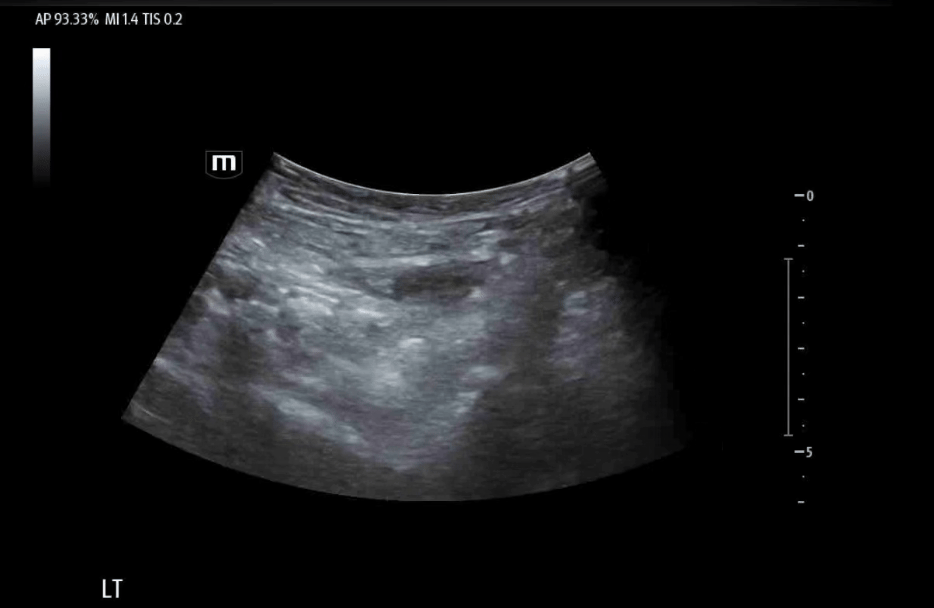

Identification of the AIIS, IPE, and femoral neurovascular bundle in the left hip